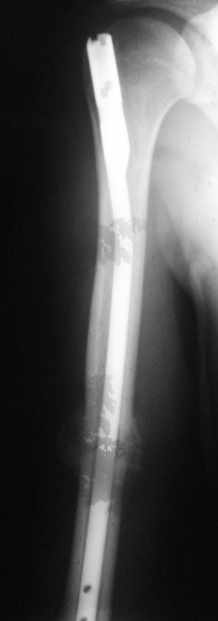

Уважаемые коллеги!Обратился пациент, оперирован не у нас.

однозначно не блокировать и не убирать - есть прекрасная мозоль и все отлично срастается. Мне плохо видно - выступает ли гвоздь проксимально ( кажется, нет, гвоздь строго в уровень с костью)?

Спасибо. А не слишком ли хороша мозоль?

Большая мозоль - здоровый организм УСПЕШНО компенсирует недостатки фиксации.

Само же состояние перелома мне не внушает никаких сомнений или опасений

Гвоздь для плеча - дело не очень хорошее, и, честно говоря, на этих снимках показаний к такому методу лечения я никаких не вижу. Больше процент несращений, часто (до 20-30 процентов) встречаются осложнения со стороны плечевого сустава... Однако, это уже выходит за пределы обсуждаемой темы

Пациент обратился с жалобой на лигатурный свищ.

Амплитуда движений 70-80% от контрлаптеральной конечности с умеренной болью в месте перелома. Наиболее болезненно - заведение руки за спину (появляется боль в области плечевого сустава). Отведение - градусов 70, далее за счет лопатки.

Обычное дело, пусть разрабатывает давно, лучше с методистом. Тут по снимкам проблем не видно. Винты вводить необязательно - если хирург знает, что делает. Например, если получился хороший press-fit из-за несоответствия формы гвоздя и канала.